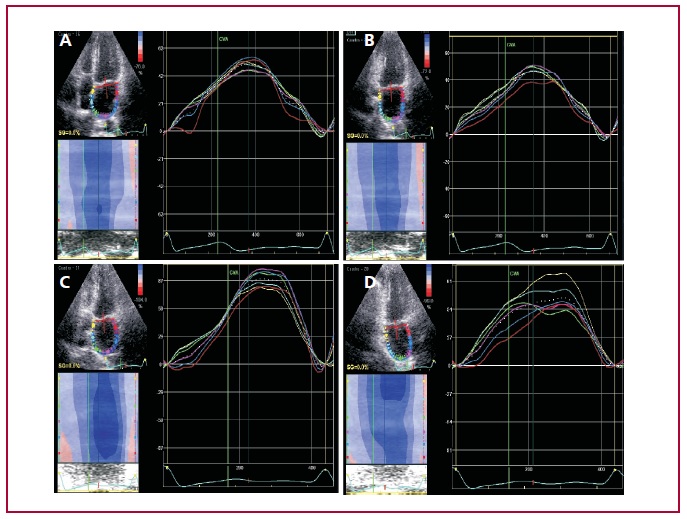

Con el advenimiento de las nuevas técnicas ecocardiográficas es posible evaluar la mecánica de la deformación de la pared auricular (strain) con curvas que identifican la función de reservorio, conducto y contracción. Sin embargo, aún no hay consenso para definir el valor de strain auricular izquierdo, determinado mediante speckle tracking, en pacientes normales y su respuesta con el ejercicio.

Se utilizó un Vivid E 95 (GE Healthcare), con transductor 5MS MHz, con adquisición de las imágenes con un frame rate entre 60-70 en reposo y entre 80-90 en el esfuerzo. Los loops se obtuvieron en las vistas de 4 cámaras y 2 cámaras, tanto en reposo como a la máxima carga de ejercicio y se analizaron offline (EchoPac Version 201). Para la medición de strain, se trazaron los bordes de la AI, a 1 mm de distancia del anillo de la válvula mitral, y se ajustó de manera manual el ancho de la zona de interés en relación con el espesor de la pared auricular. Se consideraron los 6 segmentos por cada vista y se analizó el valor promedio de la curva correspondiente al reservorio por ser la más representativa y reproducible. Para el valor de rigidez auricular se calculó el promedio E/e´/strain AI × 100. En el análisis estadístico, las variables categóricas se expresan como porcentaje y las cuantitativas como media ± DS y se comparan con la prueba de t para muestras pareadas. Se consideró significativa una p < 0,05.

Resultados: De 34 pacientes con criterios de inclusión se excluyeron a 3 por mala ventana ecocardiográfica en reposo y 2 en el esfuerzo. De los 29 pacientes analizados (factibilidad total 85%), 16 fueron hombres con una media de edad de la población de 50 ± 10,6 años. La variabilidad intraobservador del cálculo del reservorio en reposo y esfuerzo fue del 2,2 % ± 1,6 y 2,3% ± 2,5 e interobservador de 6% ± 7 y 4,6% ± 4, respectivamente.

Conclusiones: En una población normal resultó factible evaluar la función del reservorio de la aurícula izquierda en reposo y durante el esfuerzo máximo con un incremento significativo de la deformación, sin cambios de la rigidez auricular.